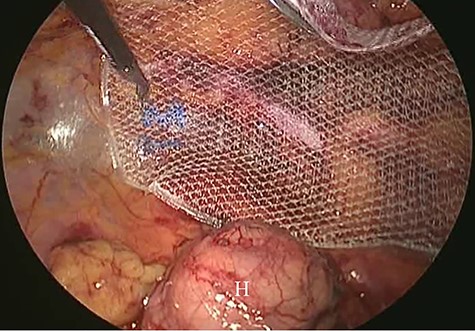

A 62-year-old woman visited our hospital with a 1-day history of lower abdominal pain and bulging from a right groin lesion. Her physical examination showed a right inguinal bulge and pain. Her abdomen was not distended and was without rebound tenderness and muscular defense. However, the bulge in the right groin lesion could not be reduced manually. Contrast-enhanced computed tomography showed a hypodense rounded lesion medial to the right femoral vessels (Fig. 1A) with fluid collection (Fig. 1B), with no intestinal obstruction or ischemia. Based on these physical and radiological findings, the patient was diagnosed as having a right incarcerated femoral hernia containing fat tissue. As there were no clear findings of intestinal obstruction, elective TEP repair was performed 1 day after admission following preoperative evaluation of her general condition. An infra-umbilical incision was made under general anesthesia. The preperitoneal space was created with blunt dissection with the aid of CO2 gas insufflation to a pressure of 12 mmHg. Two 5-mm trocars were inserted into the left mid-abdomen. The hernia sac had herniated into the right femoral canal (Fig. 2A). Therefore, we diagnosed a right incarcerated femoral hernia containing greater omentum. However, there were no findings of abscess formation or small bowel necrosis. We were able to release the hernia sac using laparoscopic forceps (Fig. 2B). After reduction of the hernia sac, 10.3 × 15.7 cm polypropylene mesh was placed in the preperitoneal space and fixed to Cooper’s ligament with a fixation device (ProTack™, COVIDIEN) (Fig. 3). Intraperitoneal observation was not performed because we considered it unnecessary to confirm the presence of intestinal damage. The patient’s postoperative course was uneventful, and she was discharged from our hospital 3 days after surgery. Presently, at 1 month after surgery, the patient is doing well without recurrence or mesh infection.

Intraoperative findings. A: The hernia sac (H) had herniated into the right femoral canal. B: The hernia sac (H) was released from the femoral canal (F) with laparoscopic forceps.